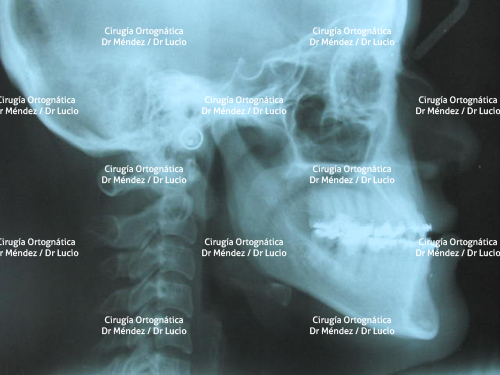

RETROGNASIA E HIPOPLASIA DEL MENTÓN Paciente operado de avance de mandíbula y mentoplastia de avance |

||

![]() |

|